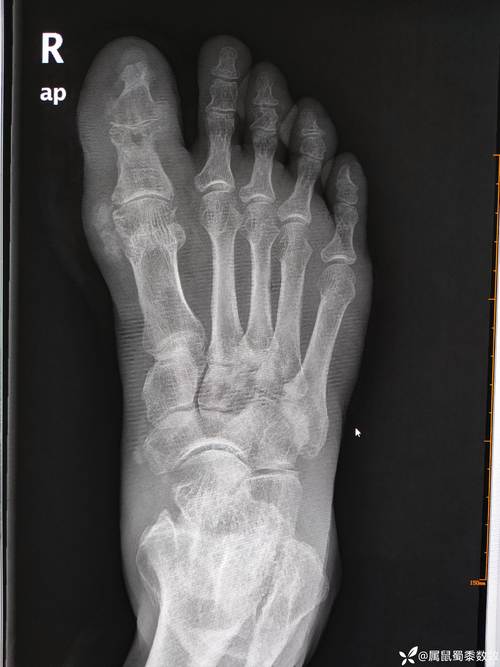

痛风石,也称为痛风结节,是痛风患者体内尿酸结晶沉积在关节和软组织中的硬块,当痛风石体积增大到一定程度,可能会出现爆裂的情况,以下是一些关于脚踝痛风石爆裂的图片描述,以及相关信息。

| 脚踝痛风石爆裂初期 | 脚踝处可见一个红色、肿胀的痛风石,表面有少量液体渗出。 |

| 脚踝痛风石爆裂中期 | 痛风石体积明显增大,表面出现裂缝,液体渗出增多,周围皮肤红肿。 |

| 脚踝痛风石爆裂后期 | 痛风石爆裂后,形成溃疡,液体渗出增多,周围皮肤红肿,疼痛加剧。 |